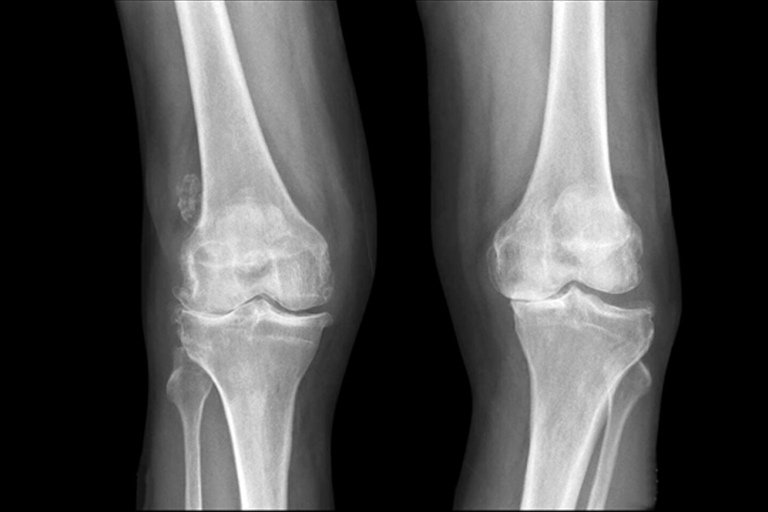

股関節・膝の痛み半月板損傷、前十字靭帯損傷、オスグッド病、ジャンパー膝、ランナー膝など

② 検査・診断

レントゲンやエコー(超音波)検査を行い、必要に応じてMRI検査(提携医療機関)を追加し、正確な診断を行います。